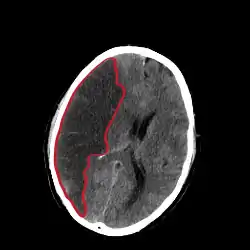

![]() تصوير مقطعي يُظِهر احتشاء في نصف الكرة المخية الأيمن (الجهة اليسرى من الصورة). تصوير مقطعي يُظِهر احتشاء في نصف الكرة المخية الأيمن (الجهة اليسرى من الصورة). | |

يُظِهر التصوير المقطعي والتصوير بالرنين المغناطيسي المنطقة المتضررة من الدماغ. وتُعطي تشخيصاً تفريقياً واضحاً يميز احتشاء الدماغ عن الحالات الأخرى التي قد تسبب أعراضاً مشابهة؛ كالأورام، نزف تحت الجافية. تصوير الأوعية أيضاً يُظِهر احتشاء الدماغ.